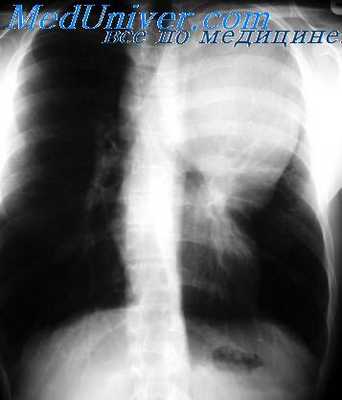

Прежде всего мы отбросили диагноз «тимома», с чем больной был направлен в институт. Против злокачественной тимомы свидетельствовало общее хорошее состояние больного без каких-либо признаков компрессии органов средостения (особенно крупных сосудов) при наличии огромной опухоли, занимающей почти все пространство от передней стенки грудной клетки до трахеи. Кроме того, на томограммах в прямой и боковой проекциях выявляется как бы конгломерат узлов, расположенных на различной глубине средостения, на что указывает и симптом «кулис».

Рентгенологическая картина с выраженным двусторонним поражением множества лимфатических узлов средостения на различной глубине давала больше оснований для диагноза лимфосаркомы.

При проведении курса рентгенотерапии оказалось, что данная опухоль довольно чувствительна к ионизирующему излучению, так как через 20 дней (после суммарной дозы в 4000 г) было отмечено значительное ее уменьшение, а через 40 дней (6000 г) она полностью исчезла.

Из литературы известно, что лимфосаркомы еще более рентгеночувствительны. Поэтому результаты рентгенотерапии при учете всех других симптомов позволяли нам остановиться на диагнозе лимфогрануломатоза, чувствительность которого примерно соответствует чувствительности опухоли в данном случае.